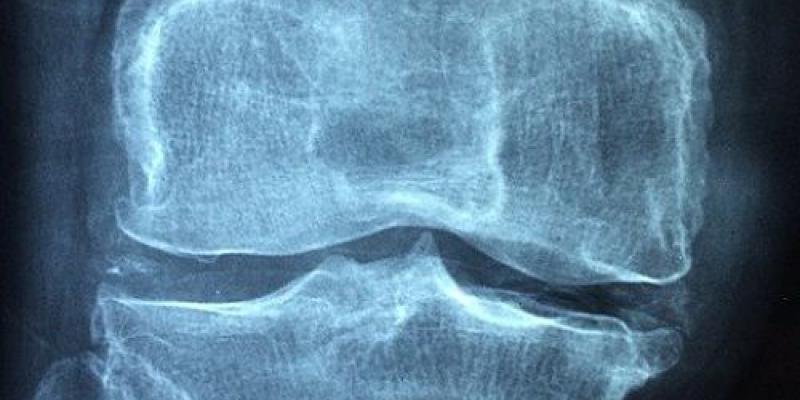

Osteoporosis/Pixabay

Qué es la osteoporosis y su principal causa

La osteoporosis es una enfermedad que se caracteriza por el deterioro de los huesos (literalmente poros o agujeros en los mismos) hasta provocar fracturas, pérdida de movilidad y, a la larga, incluso problemas psicológicos por el miedo a caídas o fracturas. La llaman la enfermedad silenciosa, ya que no se suele detectar hasta que comienzan a producirse las primeras fracturas (9 millones al año en toda Europa).

Uno de los principales problemas de la osteoporosis es que no presenta síntomas hasta que aparecen las fracturas por la pérdida de hueso. Lo más frecuente es que las fracturas se produzcan en regiones de hueso esponjoso como las vértebras (columna), la cadera o la muñeca.